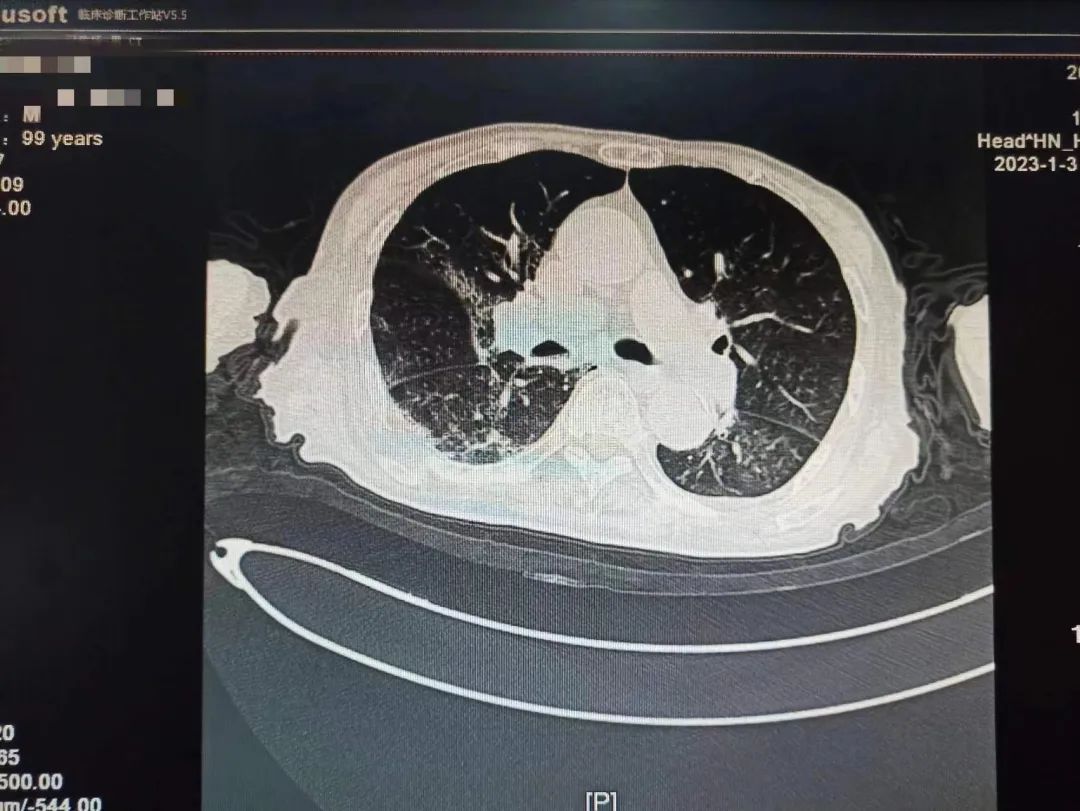

学校一附院呼吸与危重症医学科一名患者刘老爷子还差几天就到100岁生日,该患者从2022年12月22日开始持续发热,咳嗽。一开始只是以为普通的感冒,没特殊注意,后逐渐出现胸闷,乏力,精神差,在当地医院完善肺部CT,两肺大片病毒性肺炎表现,新冠核酸阳性,家属急送一附院就诊。

不放弃每一个生命!全力救治!经过连续数日医护团队的精心救治,2023年1月9日,呼吸与危重症医学科医护团队再次对老人病情进行综合评估,检查显示患者肺部病灶明显吸收,精神明显好转,可以正常活动,和感染前身体体征一致。出院当天老人握着刘家昌主任的手激动的说:“多亏刘主任了,要不是你和咱们医院医护团队,我这关是闯不过去了,我还以为我过不去这一百岁坎了。”刘家昌主任对老人和家属详细交代了出院康复指导意见及注意事项。